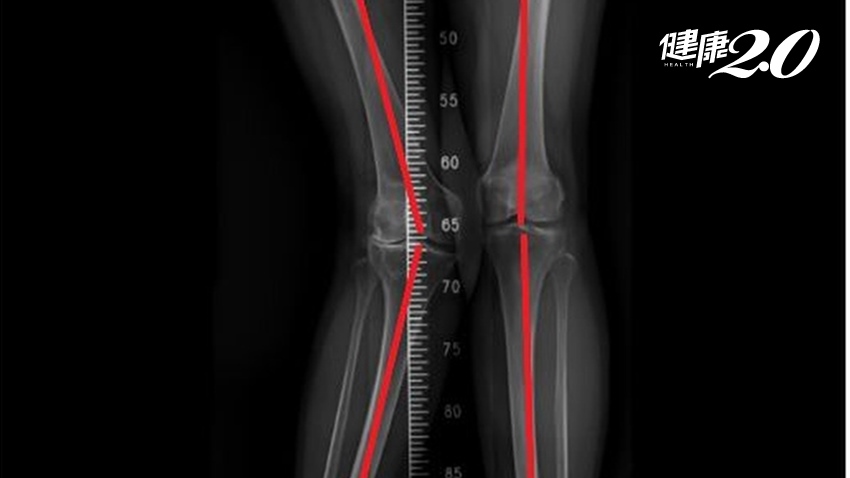

安南醫院骨科許惟傑醫師表示,膝外翻就是俗稱的X型腿,主因與老化有關。正常人雙腳站立時的膝蓋角度約5到7度,如大於10度則為膝外翻。

可依據角度大小分輕度(小於10度)、中度(10到20度)及重度(超過20度)的膝外翻,陳阿姨為35度左右故屬於嚴重膝外翻,對於手術置換人工關節難度大大提升。

▲陳阿姨的膝蓋外翻35度,屬於嚴重程度。